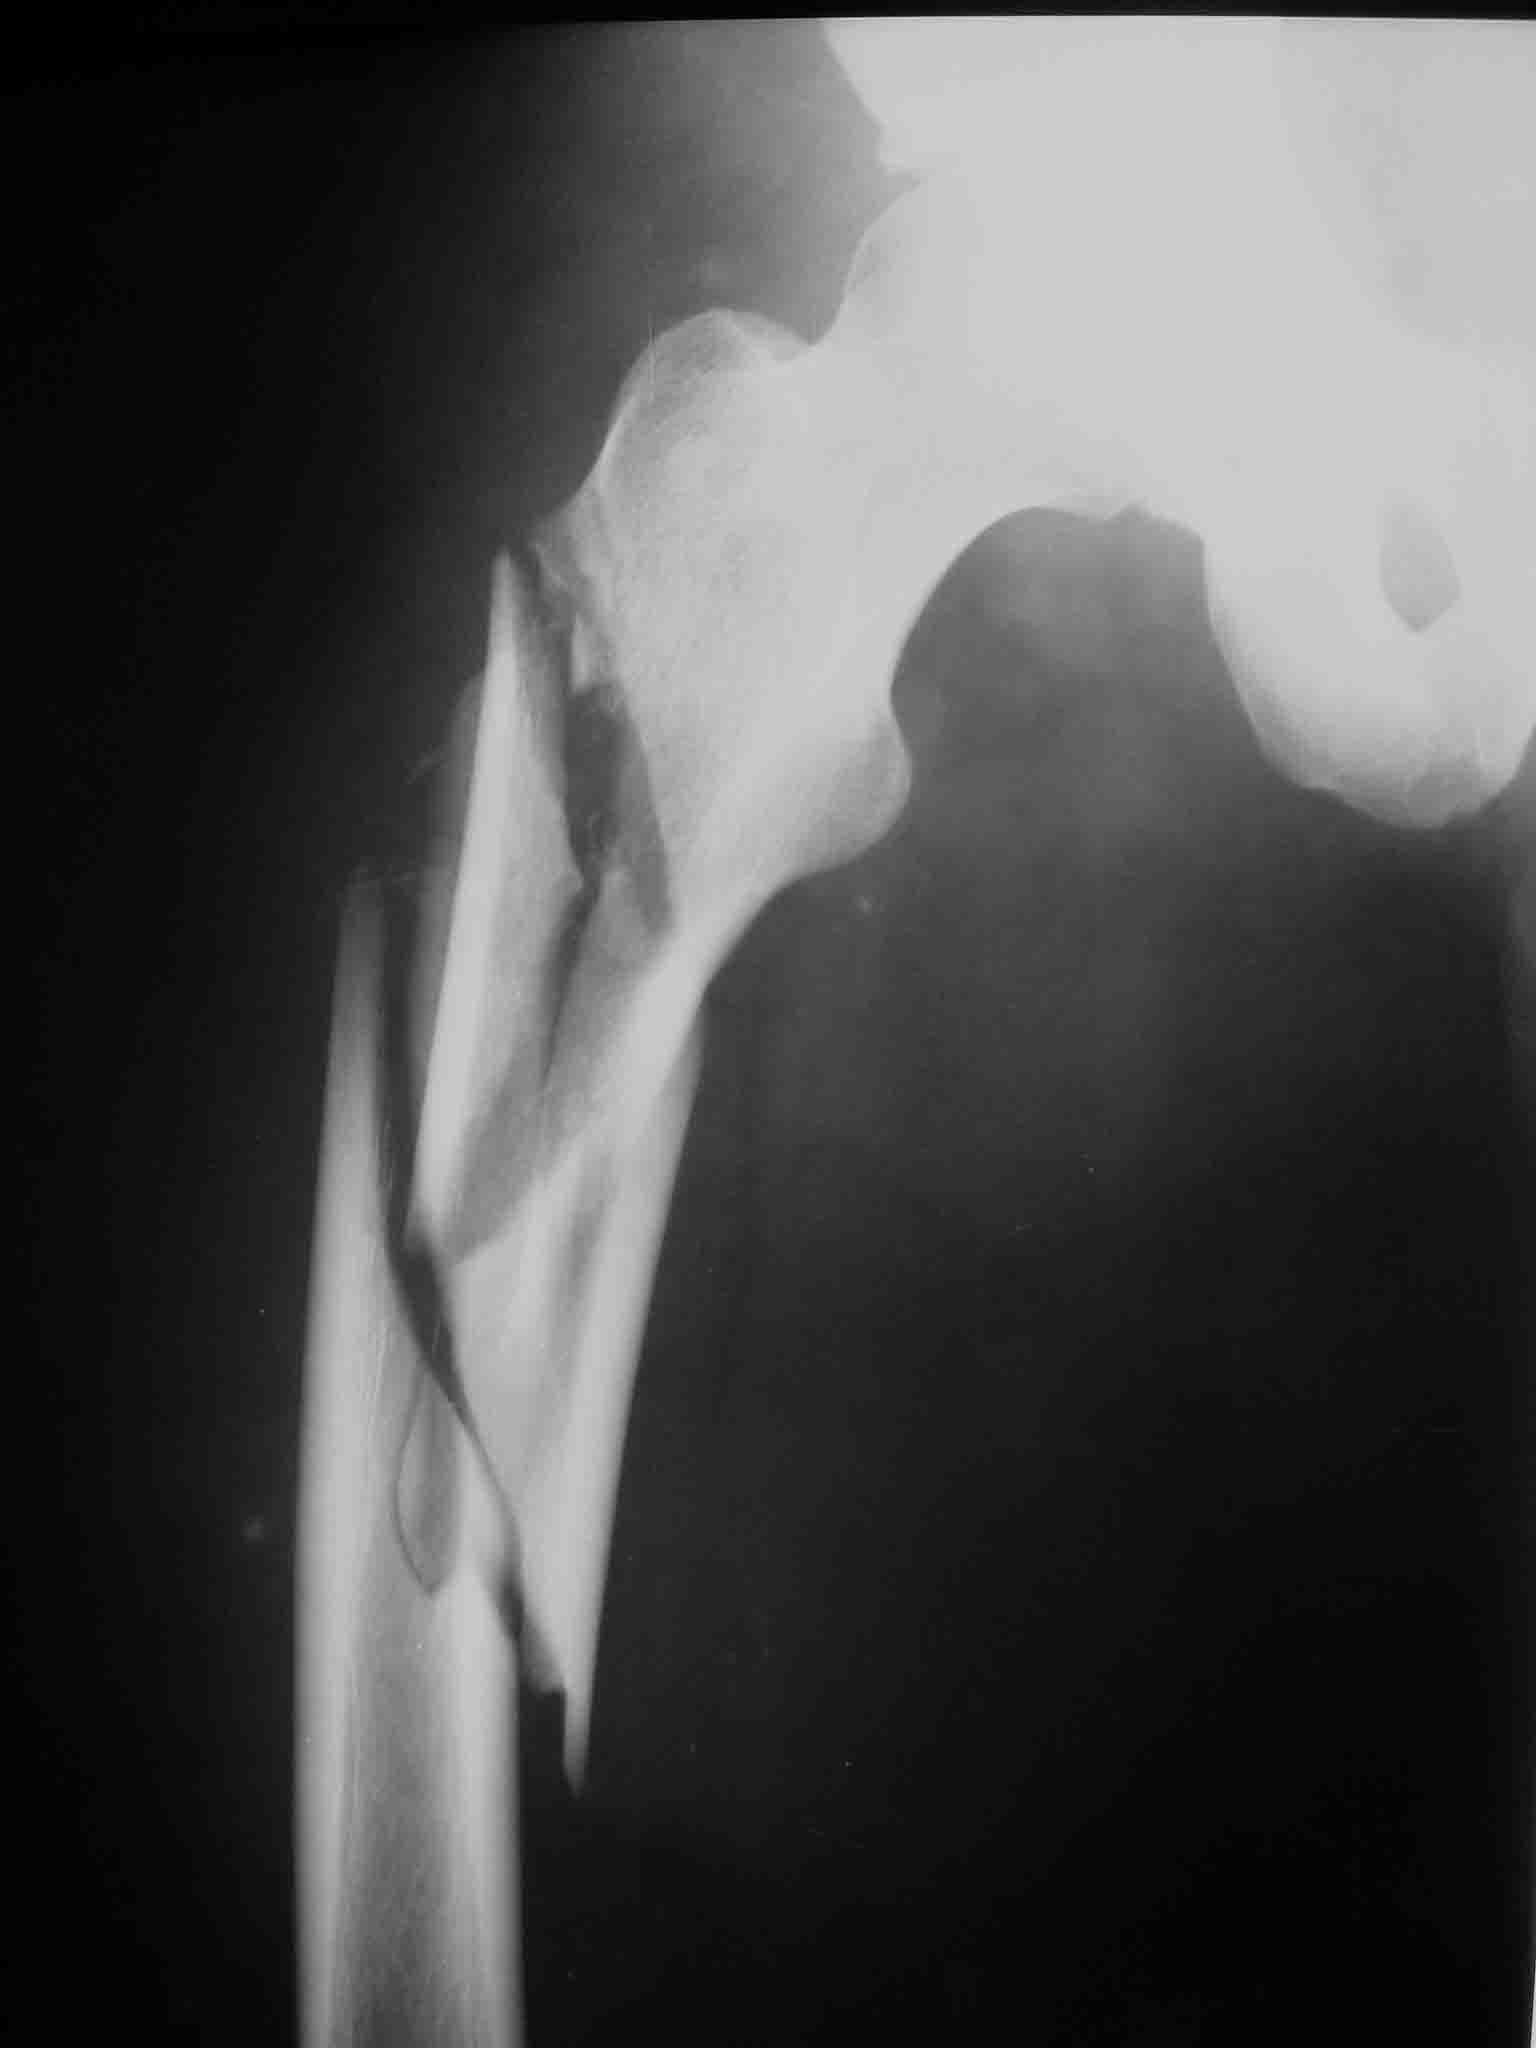

Имя     : 4.jpg

Тип     : application/octet-stream

Размер  : 50672 байтов

Описание: отсутствует

Url     : http://weborto.net:8080/pipermail/ortho/attachments/20071122/26706052/attachment-0008.obj